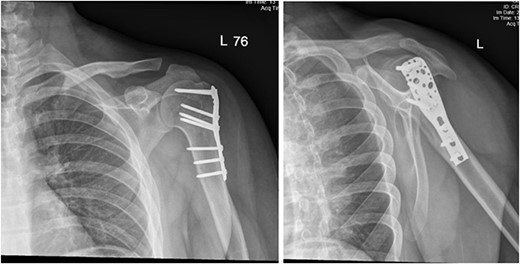

A 14-year-old boy with unknown medical and surgical history was brought by the emergency medical services to the emergency department as a case of multiple trauma after a MVA. Upon arrival, primary and secondary surveys were conducted, and management followed accordingly. After stabilization, all related specialties were involved in case management. Multiple fractures were detected, including left mandible, acetabular, open femur, and humerus fractures, as well as a comminuted pelvic fracture. The humerus fractures involved the proximal and distal area, as shown in Fig. 1.

Anteroposterior (AP) view of the left humerus and elbow pre-operative.